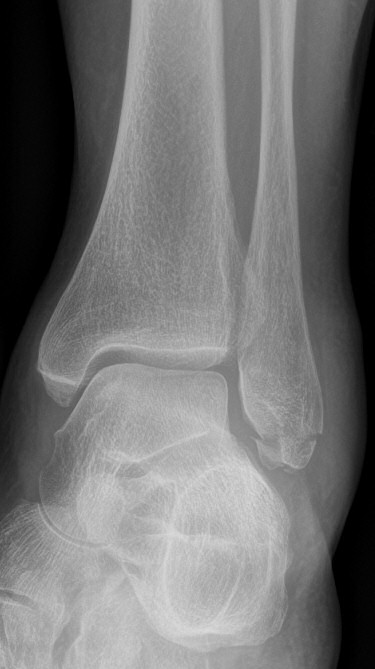

Maisonneuvefraktur

Proximal fibulafraktur (AO C3), ruptur av membrana interossea ned till fotleden och fraktur i mediala malleolen eller ruptur av lig. deltoideum.

Exempel på maisonneuvefraktur. Proximal spiralformad fibulafraktur, var svullen och ömmande runt båda malleolerna men ingen fraktur distalt.